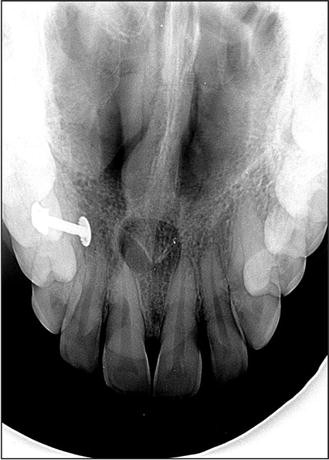

A pear-shaped and well-circumscribed radiolucent lesion with a corticated outline was found on a radiograph related to the root of an upper central incisor. The tooth was not restored and proved vital on testing.

A nasopalatine duct cyst is a specific type of cyst that develops from remnants of the nasopalatine duct. During embryonic development, this duct is involved in the formation of the nasal and oral cavities. Sometimes, remnants of this duct can persist and give rise to a cystic lesion later in life.

The nasopalatine duct extends from a structure called the incisive canal, which is located in the midline of the maxillary bone (the bone that comprises the upper jaw). The cyst can develop anywhere along this tract.